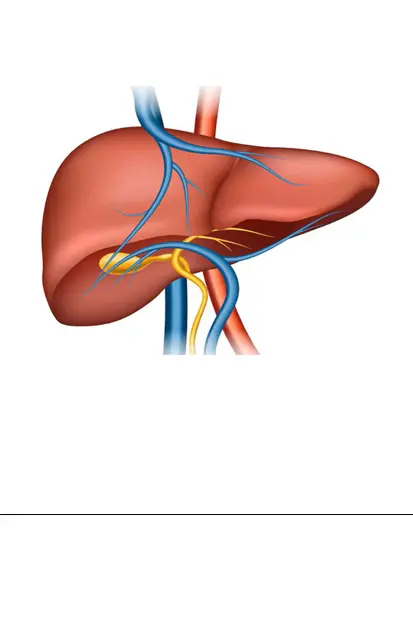

Mechanical thrombectomy (MT) can reduce disability and prevent or limit long-term care needs following a stroke.

Identifying patients eligible for MT - removing a blockage in a large blood vessel in the brain - relies on specialist radiological image interpretation. The OUH is one of 24 stroke centres across England taking part in an evaluation led by the Oxford AHSN of e-Stroke, created by Brainomix, which uses artificial intelligence (AI) technology to share high quality brain scans quickly and securely, generating unique outputs that help stroke clinicians make swift decisions relating to treatment and transfer.